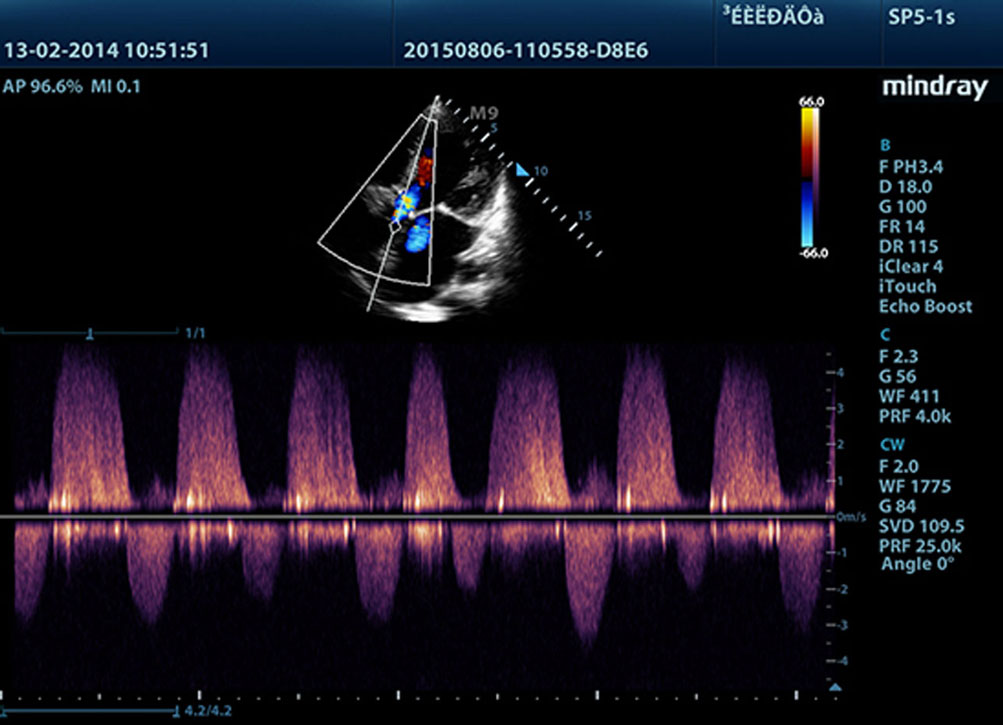

Technologie dostarczaj?ce ostrzejsze obrazy - wszystkie sondy kompatybilne z M9 s? wyposa?one w unikaln? technologi? 3T Firmy Mindray. Dodatkowo technologia Single Crystal (pojedynczego kryszta?u), oferuje lepsz? penetracj? i dynamiczny obraz przep?ywu w trybie Dopplera Kolorowego, zw?aszcza podczas skanowania trudnych przypadkÃģw.

TDI (Doppler tkankowy)

Obrazowanie Tkanek z u?yciem Dopplera - Tissue Doppler Imaging pozwala na ilo?ciow? ocen? miejscowego ruchu i funkcji mi??nia sercowego. Aparat M9 zapewnia kompletny tryb Dopplera tkankowego w celu uzyskania szybszej i bezpo?redniej diagnozy.